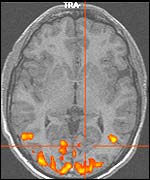

Brain scan (copyright University of Leicester)

Seeing what happens in the brain will enable scientists to learn more about sight disorders

The researchers will also look at the eye movement disorder nystagmus, where the eyes continually "wobble".

This means some people see a continually moving world, but for others things appear normal and stationary.